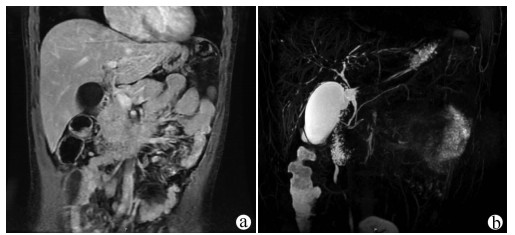

A case of splenic arteriovenous fistula with abdominal pain and gastrointestinal bleeding as the first symptoms

Yuanyuan CAI, Zhongwen WU, Juan LU

2021, 37(5): 1186-1188. DOI: 10.3969/j.issn.1001-5256.2021.05.043

Abstract(1011) HTML (291) PDF (2876KB)(49)

Abstract: